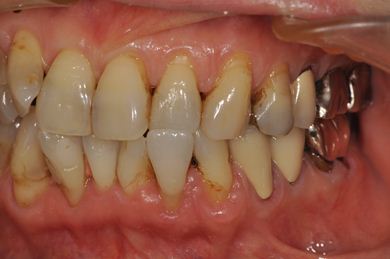

抜歯即日スピードインプラント+セラミック治療

| 性別/年齢 | 女性 / 52歳 | ||||||||||||||||||||||||||||||||

| 主訴 | 引っ越しで治療が途中になっている歯の治療と、他の歯にもトラブルが起こったため相談したい。 | ||||||||||||||||||||||||||||||||

| 治療内容 | インプラント2本(抜歯即日スピードインプラント)、ハイブリッドセラミッククラウン5本(セラミック用土台2本)、ハイブリッドセラミックインレー1本 | ||||||||||||||||||||||||||||||||